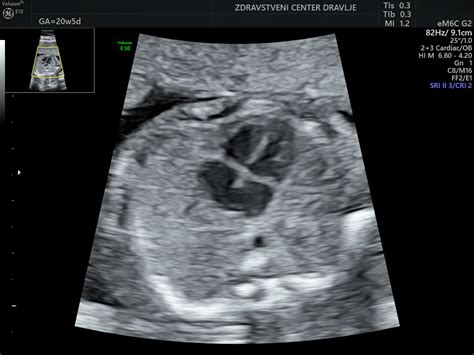

Čeprav je mogoče plodovo srce ultrazvočno pregledati in oceniti že okoli 16. tedna nosečnosti, največ pregledov opravimo pri nosečnicah med 20. in 22. tednom nosečnosti. Srce je v tem času veliko približno kot lešnik. Pregled začnemo z oceno velikosti srca in njegove lege v prsnem košu. Prikažemo priliv obeh votlih ven v desni preddvor ter priliv vsaj ene pljučne vene v levi preddvor. Razpoznamo oba preddvora in prekata ter ocenimo delovanje trikuspidne in mitralne zaklopke. Prikažemo in vrednotimo tudi ovalno okence in Botallov vod. Obe strukturi sta pri plodu široko odprti, po rojstvu pa se zapreta. Poleg same morfologije ocenimo ob ultrazvočnem pregledu plodovega srca še funkcijo srčne mišice in opredelimo srčni ritem.